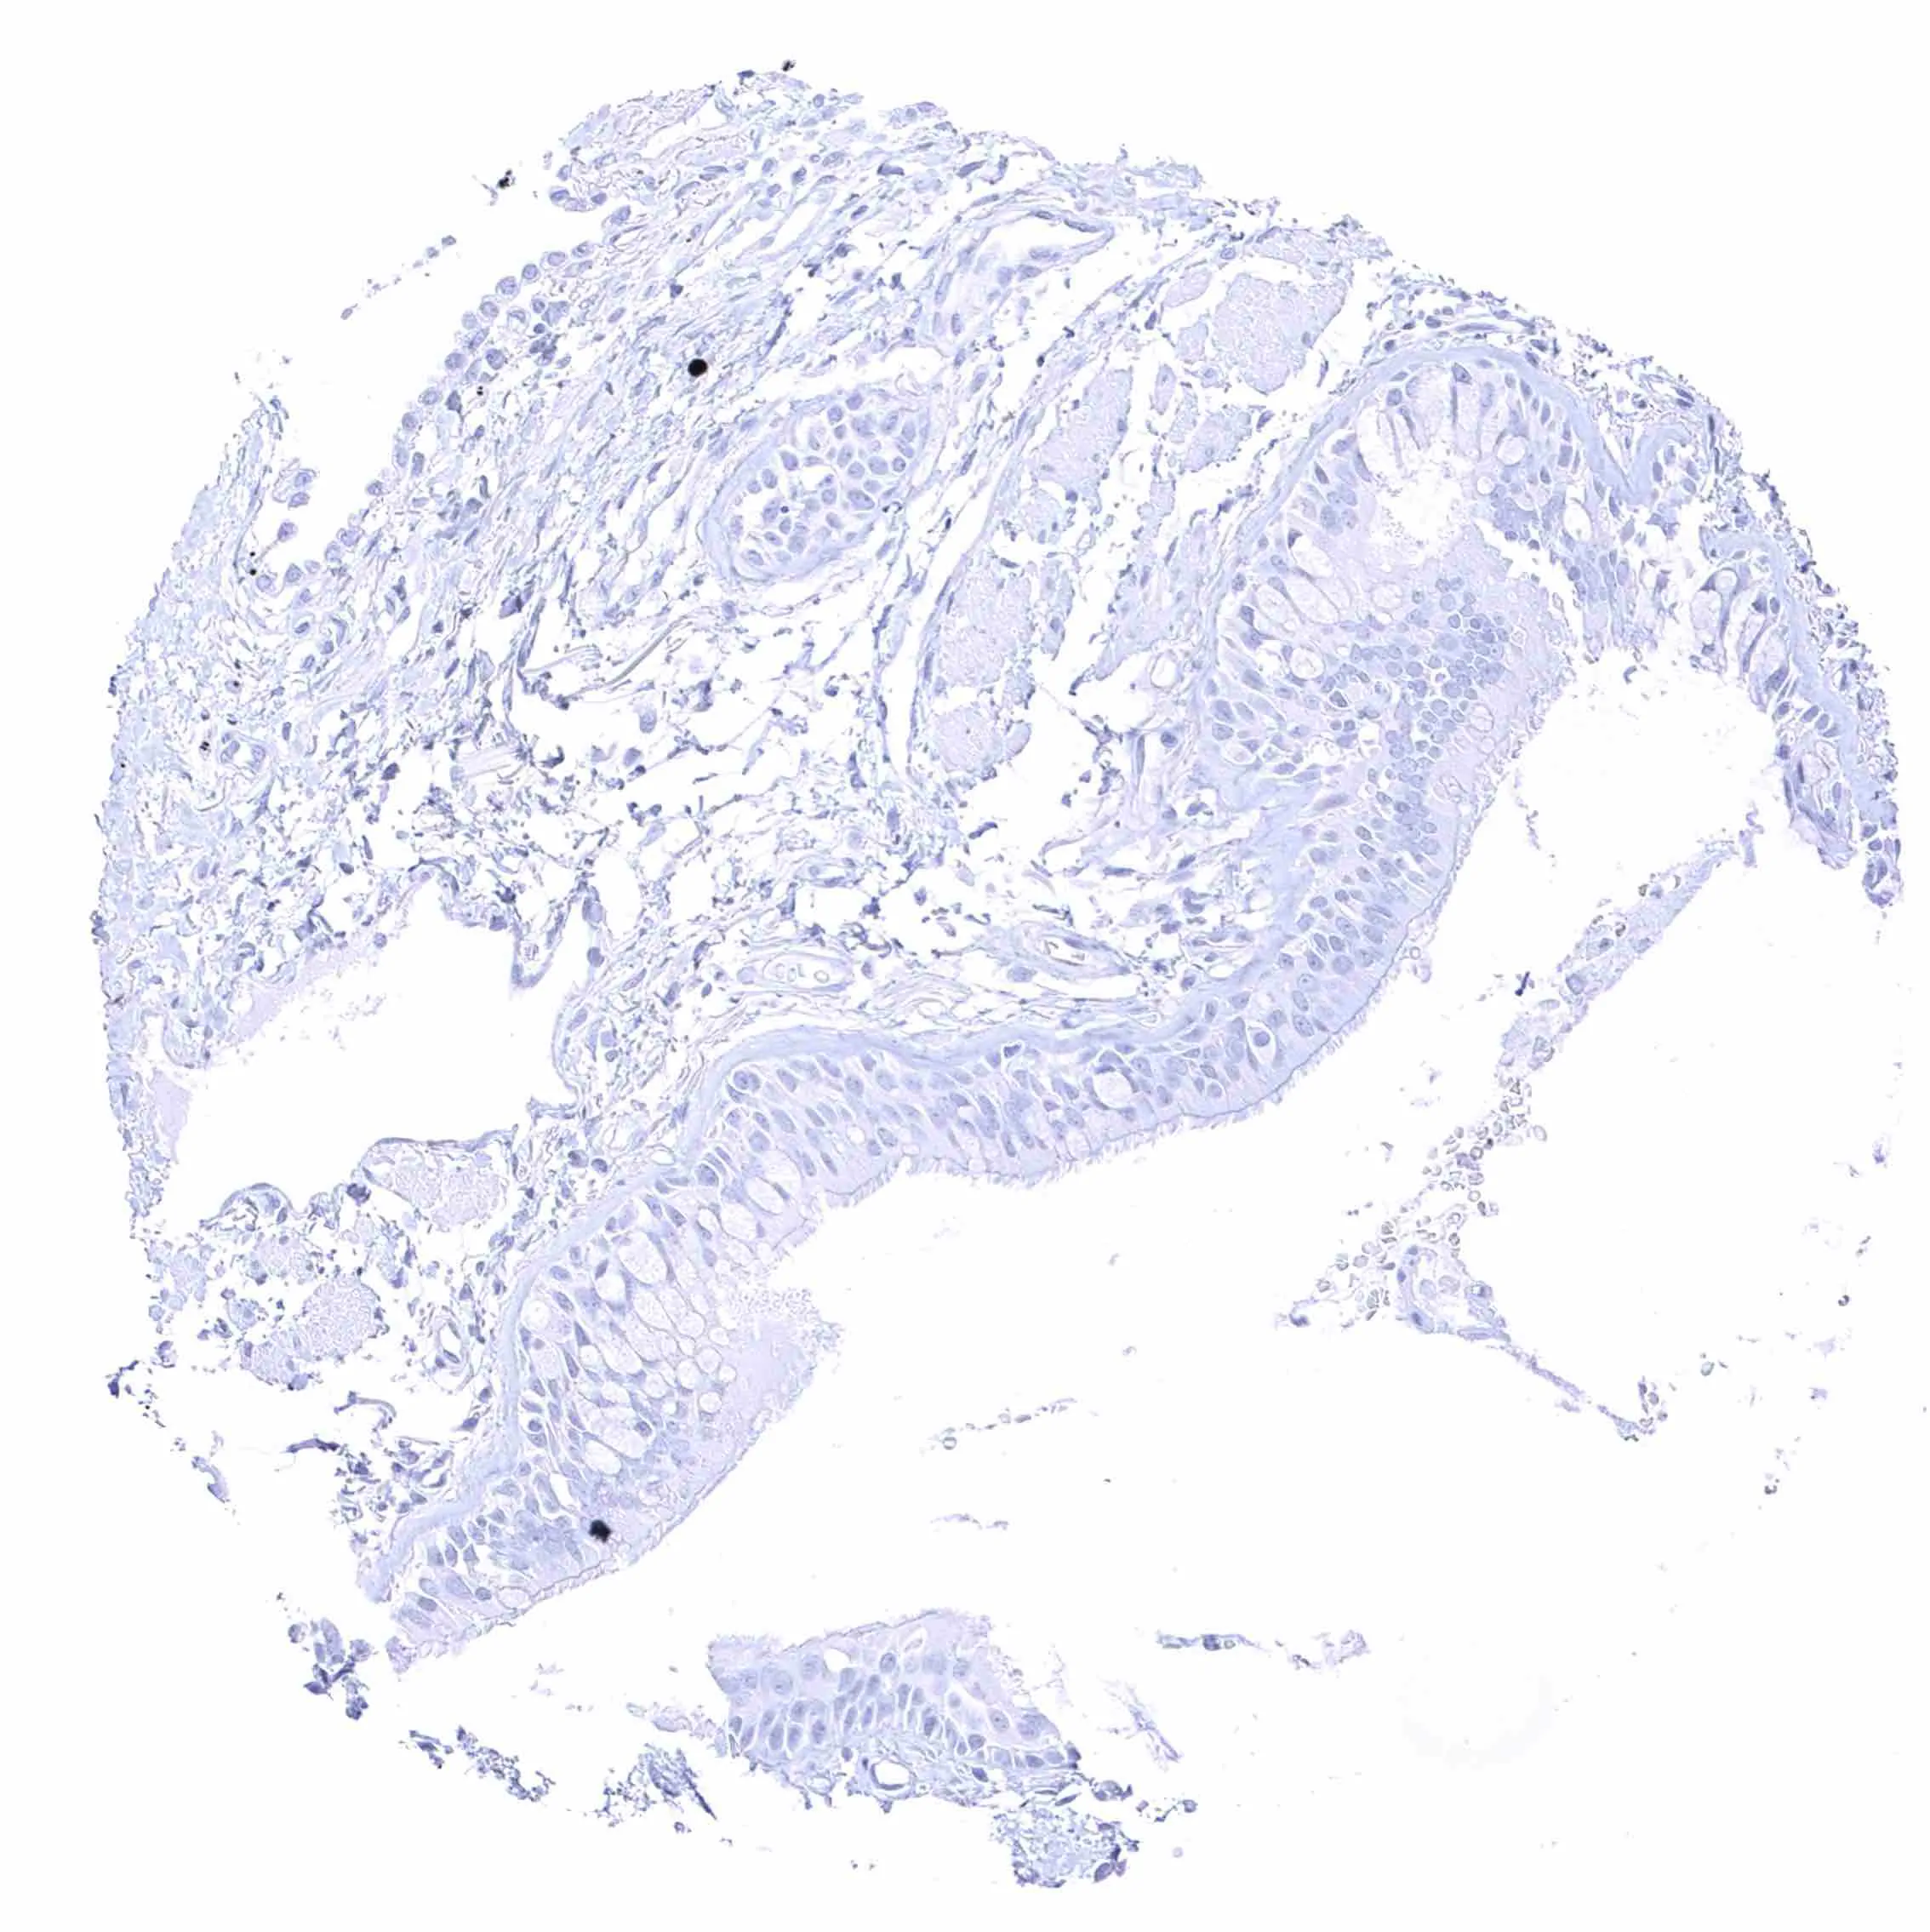

Uterus, endocervix

Uterus, endometrium (pregnancy)

Uterus, endometrium (proliferation)

Uterus, endometrium (secretion)